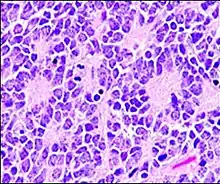

Micrograph of an ameloblastoma showing characteristic palisading. H&E stain.

In histopathology, a palisade is a single layer of relatively long cells, arranged loosely perpendicular to a surface and parallel to each other.[1] A rosette is a palisade in a halo or spoke-and-wheel arrangement, surrounding a central core or hub.[2] A pseudorosette is a perivascular radial arrangement of neoplastic cells around a small blood vessel.[2] Rosettes are characteristic of tumors.